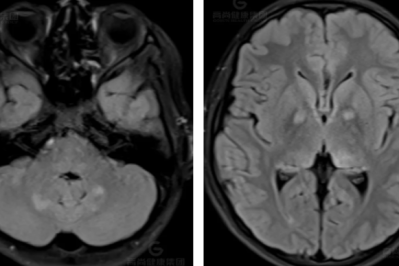

【高尚病例】脑膜瘤

2026-02-11